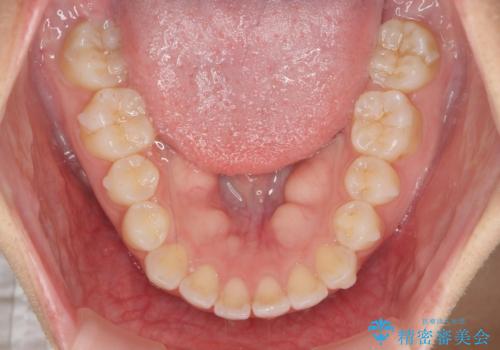

前歯のすれ違い インビザラインで行うマウスピース矯正

- 前歯のガタつき、でこぼこ、前後が逆になっている噛み合わせの改善を求めて来院されました。

治療の装置が目立たず歯ブラシのしやすいマウスピース矯正インビザラインでの治療を計画します。

20時間/日の装用時間をしっかりと守っていただき、きれいな歯並びを手に入れることができました。